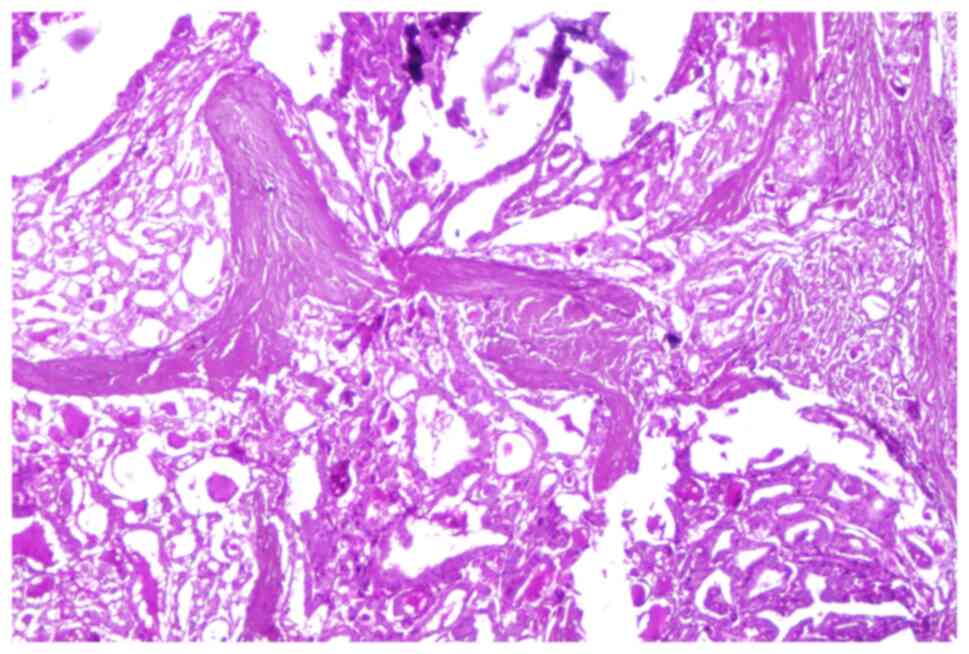

Cytomorphological study of thyroid carcinoma

The most common neoplasm of the endocrine system is found in the thyroid gland with a significant increase in recent decades largely due to modern diagnostic methods. Thyroid tumors generally have a favorable evolution, but there are also aggressive variants with a poor prognosis. In these aggressive tumors, the most reliable method of detecting and making a differential diagnosis is represented by ultrasound‑guided fine‑needle cytopuncture, confirmed by histopathological examination. Although fine‑needle aspiration puncture and cytological examination are considered to have a high sensitivity and specificity, diagnostic certainty is established later only by histopathological examination. Fine‑needle aspiration cytopuncture of the thyroid gland correlated with histopathological examination has played a crucial role in recognizing and identifying variants of papillary carcinoma known to have aggressive biological behavior, especially in cases of poorly differentiated carcinoma. Recognition of aggressive variants of papillary carcinoma is of major importance in the prognosis and clinical management of patients. The aim of this study was to present the correlations found in a series of thyroid tumors from patients treated in surgery and oncology departments, as well as tumors accidentally detected during autopsies in the department of forensics. All the cases selected in the study benefited from a complex histopathological diagnosis adapted to each case in order to ensure maximum efficiency.